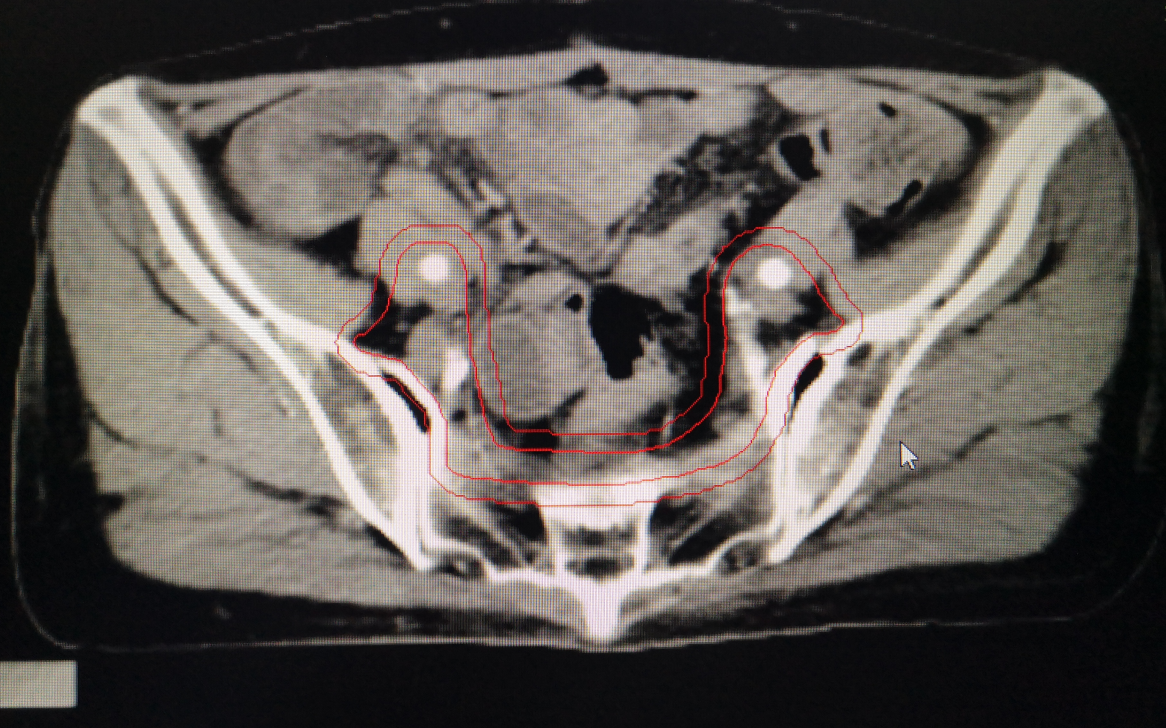

婦科腫瘤術後勾畫靶區示例: